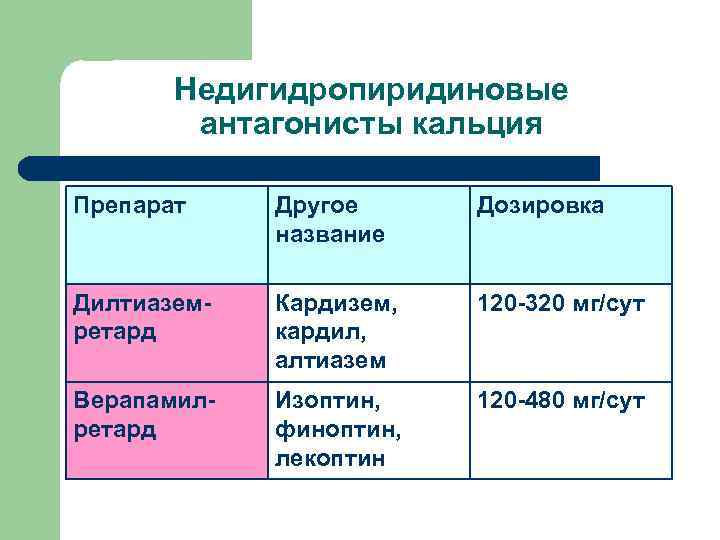

Недигидропиридиновые антагонисты кальция Препарат Другое название Дозировка Дилтиаземретард Кардизем, кардил, алтиазем 120 -320 мг/сут Верапамилретард Изоптин, финоптин, лекоптин 120 -480 мг/сут